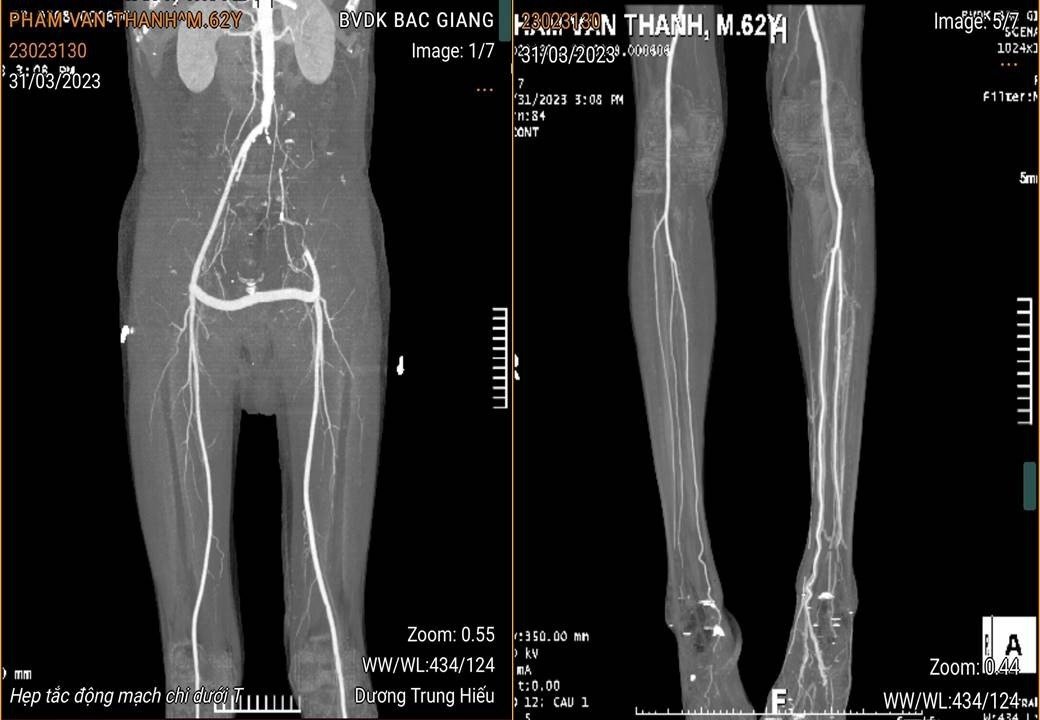

Ngày 21/3/2023, Bệnh viện Đa khoa tỉnh Bắc Giang tiếp nhận từ Bệnh viện Đa khoa Sơn Uyên (Hiệp Hòa) nam bệnh nhân P.V.T ( 62 tuổi, địa chỉ tại Hùng Sơn, Hiệp Hòa, Bắc Giang) trong tình trạng đau cẳng chân trái; tê bì nhiều; da khô, tái lạnh; đau nhiều và bầm tím bàn chân, ngón chân khi đi lại. Theo lời người nhà kể, người bệnh có tiền sử hút thuốc lá nhiều năm và đã phát hiện tắc động mạch chậu đùi trái cách đây hơn 01 năm. Dạo gần đây, thấy chân có dấu hiệu đau nhiều, cứ đi lại vài bước là đau, ngồi thì đỡ nên người bệnh đến bệnh viện tuyến dưới khám và được chuyển xuống Bệnh viện Đa khoa tỉnh điều trị.

Sau khi nhập viện vào khoa Ngoại lồng ngực –Chỉnh hình- Bỏng, người bệnh được thăm khám và làm các cận lâm sàng cần thiết. Kết quả siêu âm doppler mạch máu phát hiện bệnh nhân tắc động mạch chậu đùi trái, tắc động mạch khoeo chân trái, khả năng cấp máu bàn chân trái giảm nặng.

Người bệnh được chẩn đoán tắc động mạch chậu đùi trái mãn tính và tắc động mạch khoeo trái bán cấp tính. Các bác sĩ đã cân nhắc giai đoạn bệnh với tình trạng hiện tại của người bệnh và thống nhất phương pháp điều trị tối ưu nhất là phẫu thuật bắc cầu động mạch đùi- đùi bằng đoạn mạch nhân tạo, mở động mạch khoeo lấy huyết khối. Kíp phẫu thuật do Bs.CKII Nguyễn Văn Nam, Trưởng khoa Ngoại lồng ngực CH-Bỏng; Ths Đỗ Văn Dũng, PTK Phẫu thuật gây mê hồi sức cùng các cộng sự thực hiện. Sau 90 phút đồng hồ, ca phẫu thuật đã được thực hiện thành công. Chỉ sau 12h phẫu thuật, tình trạng đau của bệnh nhân được cải thiện, hết cảm giác tê, xờ bàn chân, ngón chân ấm, mạch chân trái bắt rõ hơn, tình trạng tưới máu cẳng bàn chân trái được lưu thông. Hiện tại, 10 ngày sau phẫu thuật, người bệnh đã ổn định và được xuất viện về nhà.